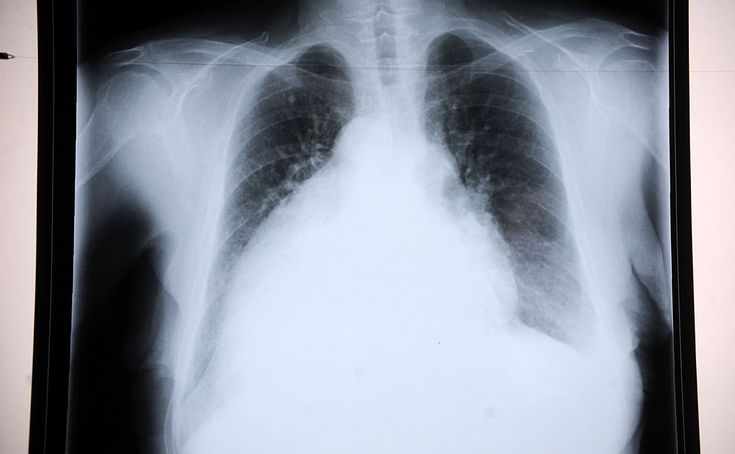

«Plaušu transplantācija ir ļoti dārgs pasākums. Vienas plaušas transplantācija varētu izmaksāt apmēram 300 000 eiro,» VC4 «Capital Clinic Riga» torakālais ķirurgs, bronhologs Artjoms Špaks sacīja RīgaTV 24 raidījumā «Nākotnes medicīna», atklājot to, ka Latvijas ārsti ir tehniski gatavi veikt plaušu transplantācijas operāciju.

Pirmā problēma ir finansējums. «Plaušu transplantācija ir ļoti dārgs pasākums. Vienas plaušas transplantācija varētu izmaksāt apmēram 300 000 eiro,» atklāja bronhologs. Viņš norādīja, ka jāņem vērā arī pēcoperācijas periods un ar to saistītās izmaksas: «Izmaksas medikamentiem un pārbaudēm ir ap 30 000 mēnesī.»

Otra problēma esot rezultāti un operācijas efektivitāte. «Diemžēl 5 gadu dzīvildze ir tikai 50% šo pacientu. Arī nevarētu teikt, ka dzīves kvalitāte dramatiski uzlabojas,» apgalvoja Špaks.

Viņš gan atklāja, ka ar šo problēmu saskaras visā pasaulē: «Tā ir visas Eiropas un pasaules problēma. Diemžēl no pacientiem, kam tiek transplantēti orgāni, rezultāti plaušām ir vieni no sliktākajiem.»